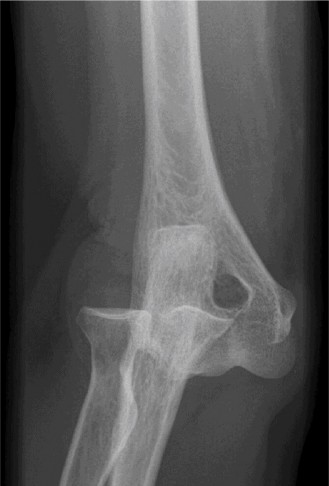

Treat a patient with infected total shoulder arthroplasty? CASE 21 A 70-year-old, right-hand-dominant female presents to clinic complaining of 4 years of gradually worsening chronic right shoulder pain and stiffness. She says the pain is worse at night and with any range of motion, denies a history of trauma, pain in other extremities, or numbness or tingling of the right upper extremity. She notes that her mother suffered from rheumatoid arthritis that affected her shoulder. Physical examination reveals decreased muscle bulk over the right supra- and infraspinatus fossae compared to the contralateral side, limited active and passive ROM, marked weakness with external rotation, and 4+/5 strength with shoulder abduction. X-rays of the right shoulder are shown in Figures 2–58 and 2–59.

The correct answer is (C). Rotator cuff tear arthropathy consists of a combination of rotator cuff insufficiency, glenohumeral joint degenerative changes, and superior humeral head migration. It is more common in women and also more often found on the dominant side. The patient’s clinical examination with weakened external

rotation and muscle atrophy signaling incompetent supra- and infraspinatus muscles point to rotator cuff insufficiency, and her plain films reveal narrowed glenohumeral joint space as well as superior migration of the humeral head. Choice D is incorrect because, while radiographs would show narrowing of the glenohumeral joint space, they would also likely show numerous osteophytes and posterior wear of the glenoid. Choice B is incorrect because, while adhesive capsulitis does present as decreased active and passive range of motion, the patient’s constellation of symptoms pointing towards rotator cuff insufficiency along with the radiographs make cuff tear arthropathy the more likely choice. Finally, Choice A is incorrect because even though she has a positive family history of rheumatoid arthritis, it is less likely to present only in a single joint. Also, rheumatoid arthritis on radiography appears more as an erosive process without the characteristic superior migration of the humeral head.

The correct answer is (A). Superior migration of the humeral head would be most indicative of chronic rotator cuff insufficiency associated with cuff tear arthropathy, as it is a direct result of the inability of the rotator cuff tendons to help maintain the humerus in its normal position. Acetabularization of the undersurface of the acromion is commonly associated with superior migration of the humeral head found in rotator cuff tear arthropathy, and can be assessed using the Hamada classification, which is based on measurements of the acromiohumeral interval on radiography (Table 2–8). Choices B and C are incorrect because, while narrowed glenohumeral joint space and subchondral sclerosis are associated with rotator cuff arthropathy on radiographs, they indicate degenerative joint changes rather than chronic rotator cuff insufficiency. Choice D is incorrect because it is not a specific sign of rotator cuff arthropathy.